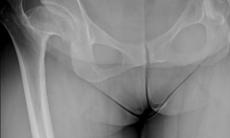

Trei operatii de protezare bilaterala, intr-un singur timp operator

Prima interventie a constat in montarea a doua proteze in cazul unei paciente in varsta de 46 de ani, cu sold displazic bilateral care a insemnat inegalitate de membre, durere si dificultati de...